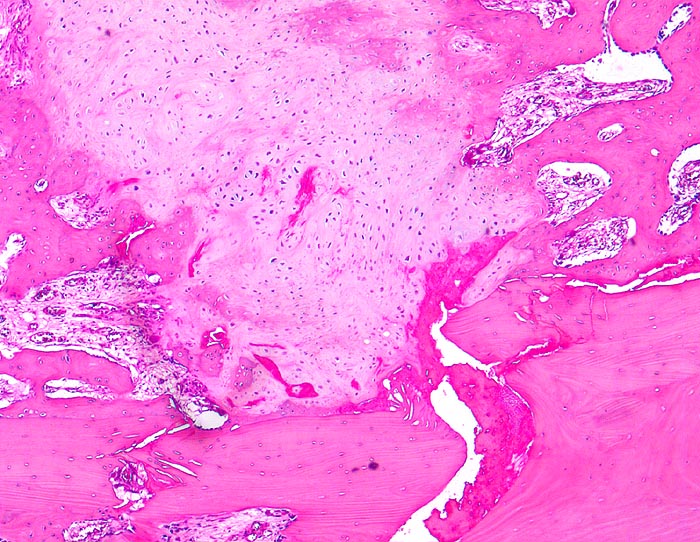

sekundäre Frakturheilung: Frakturspalt

Knochen, Rippe

Frakturspalt mit Fibrinablagerungen und neugebildetem, teils mineralisiertem Knorpel. Devitalisierter ortsständiger Knochen mit leeren Osteozytenhöhlen. Markraumfibrose.

Konservativ behandelte Rippenfraktur nach Sturz vor einem Monat.

Der Nachweis von neugebildetem Knorpel entlang der Frakturlinie im Innern des Knochens ist ein Charakteristikum vor allem der Rippenfraktur als Folge einer mangelhaften Ruhigstellung. Die notwendige Resorption des avitalen Knochens führt zu einer Heilungsverzögerung.

160